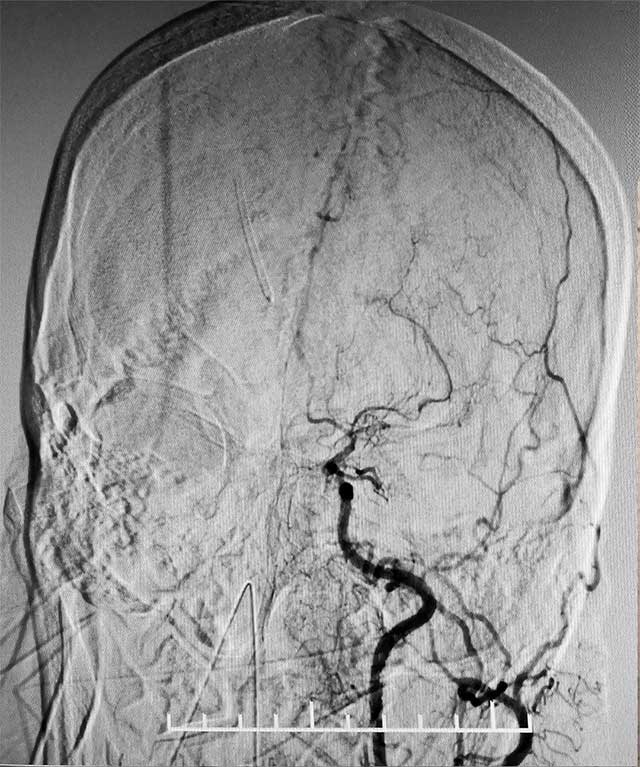

▲ 术前造影显示,患者双侧颈内动脉末端闭塞,颅内烟雾状血管形成

患者是一位59岁女性,近一个月前,无明显诱因出现恶心、喷射性呕吐,随即意识不清,送至当地医院急诊,行头颅CT:脑室系统出血,立即于全麻下行脑室钻孔引流术+储液囊置入术。术后患者病情平稳但神志嗜睡,处于浅昏迷状态。

经脑血管CTA和DSA检查,结果显示,患者双侧颈内动脉末端闭塞,左侧大脑中动脉闭塞,颅内烟雾状血管形成,左侧颞顶枕叶灌注不足明显,颅底出现细如烟雾的代偿血管网络,脑部供血严重不足。结合病史,患者部被确诊为烟雾病,由于代偿血管壁长期受到异常血流冲击,形成动脉瘤导致脑出血。张琪博士决定为其实施复合手术室下颅内外血管搭桥联合硬脑膜翻手术。由于患者脑血流非常薄弱,任何风吹草动,都有可能出现脑梗、脑出血。另外,在手术过程中,在全身麻醉状态下,可能出现血压降低,造成脑梗。所有这些无疑增加了手术难度和风险。